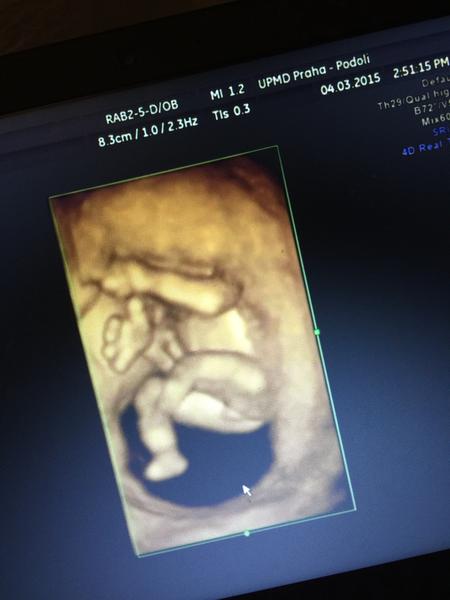

Je to holčička nebo chlapeček? Foto ultrazvuku

Ahoj maminky a budoucí maminky 😉 Prosím, poradila byste mi některá, co vidíte na fotce z ultrazvuku ve 20. týdnu za pohlaví? Určitě jste foteček viděly už mraky, proto vás žádám o radu...Nechci nikoho ovlivnit, proto svůj tip řeknu později 🙂 Děkuju moc!!!

Teda moc dekuji za názory paní doktorka nám tvrdí holčička,ze tam nic nevidí nic nenarostlo to jsem tedy napjatá :*

Myslíte tedy? Mam sice dvě deti,ale jeste ani jednou takto 3D jen u dcerky a to az ve 25 tydnu kdy uz to bylo opravdu videt,ale říka se,že v tom 17-18 tydnu uz by to mělo byt videt 🙂